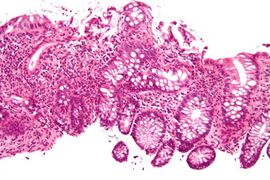

Additional images

Focal cryptitis and a granuloma. H&E stain.